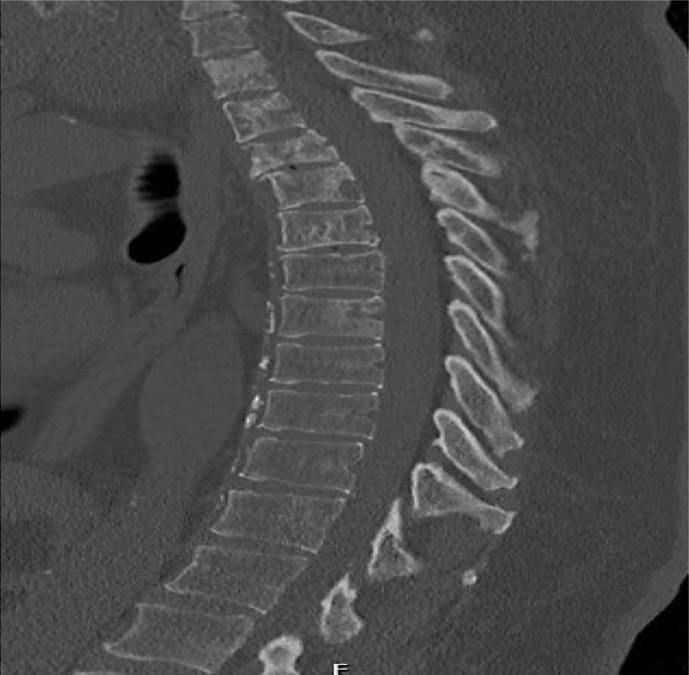

Case presentation: A 60-year-old male with a significant smoking history and breast cancer presented to the emergency department with severe back and left lower extremity pain. Clinical evaluation revealed an erythematous lesion near the left nipple. Imaging and biopsy confirmed worsening metastatic breast carcinoma involving multiple vertebral bodies. The patient previously received hormonal and targeted therapies but discontinued treatment due to lack of resources, insurance issues, and follow-up associated with breast cancer diagnosis. Upon reinitiating treatment and receiving palliative radiation, the patient showed significant clinical improvement, demonstrating a complete metabolic response on follow-up imaging.